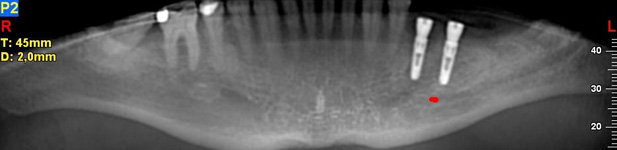

NewTom Implant Planning na plánování vhodných pozic pro zavedení implantátů. Dalším plánovacím softwarem, který umožňuje i zhotovení operačních šablon pro přesné zavádění implantátů - tzv. navigovaná implantologie, je software

coDiagnostiX od firmy Dental Wings (Německo).

Pomocí počítačových programů – NewTom Implant Planning a coDiagnostiX si lékař sám provádí veškerá potřebná zobrazení a měření.

Lékař si vytvoří všechny typy zobrazení potřebných pro naplánování – tedy 2D snímky (panoramatický), příčné řezy i 3D model.

Vidí zde i důležité anatomické útvary – čelistní dutinu, průběh nervu atd. Po proměření množství kosti – šířky i výšky vybere z databáze vhodný typ implantátu a umístí ho do požadované lokality.

Ihned vidí jeho pozici ve všech 3 rovinách a na všech snímcích i 3D modelu. Může upravovat podle potřeby jeho pozici, sklon atd.